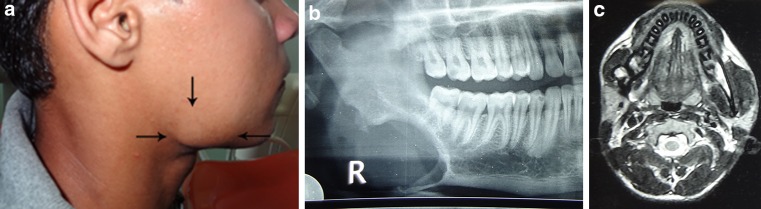

An 18 year old male patient reported to us with recurrent dull pain and gradually increasing swelling in right mandibular angle region since 6 months. There was no other associated symptom except few episodes of low grade fever. On examination there was an extraoral swelling of 3 cm × 2 cm over right angle region. The swelling was soft in consistency but appeared to be submasseteric as masseter could be palpated over swelling on clenching. Earlobe was non-everted and no salivary gland abnormality was noticed. Right submandibular nodes were palpable but non-tender. Intraoral findings were normal. Orthopantomogram revealed a non-sclerotic, well defined radiolucency at angle of the mandible which was more of roundish shape (Fig. 1a). Systemic examination, past medical history and family history were non contributory. Aspiration of the lesion was negative. Hematologic investigations including thyroid profile were all in normal range. Magnetic resonance imaging was performed. It revealed well defined, round to oval area of altered signal intensity which appeared hypointense in T1 and hyperintense in T2 window at posterior aspect of angle of mandible (Fig. 1b). Incisional biopsy was done intraorally but was inconclusive with remarks stating “Fibrovascular connective tissue with hemosiderin pigment deposit, the sample may not have been from representative site”. Ultrasound guided trucut biopsy was done to no advantage and similar findings were observed under microscope. We were not sure of the character of the lesion but concluded that it was benign and patient was posted for excisional biopsy under general anesthesia. The mass was tumorous, non-encapsulated, merging into adjacent tissues, neither firm nor soft with greenish-brown colour located under the masseter and occupied uniformly resorbed mandibular defect (Fig. 2a, b). The resorption pattern of the bone did not give an impression of resorption by an extrinsic mass (which usually exhibits saucerised resorption pattern). The mass was firmly attached to the resorbed bone as well as it had created a tunnel between buccal and lingual cortices in the surrounding bone giving an impression of intra-bony centrifugal resorption (Fig. 2a). Histological examination revealed dense fibrous collagenous tissue with few dilated capillaries and heavy deposition of hemosiderin pigment (Fig. 3a, b).

Fig. 1.

a Preoperative presentation of swelling at right angle of the mandible. b Preoperative OPG of the patient showing bone loss at angular region of the mandible. Pointed bone ends can be appreciated around foci of bone loss. c T2 weighed MRI image showing enhancement of the lesion

With regards to diagnostic work-up, radiographic aids in form of plain radiographs, radioisotope bone scans, computed tomography and magnetic resonance imaging have been utilized. Initial radiographic findings may infer patchy bone loss as seen in osteoporosis. Later stages exhibit partial to complete dissolution of the cortical structure leading to pointed ends on either side of ‘vanishing foci’. This dissolution may extend beyond the immediate joint to involve adjacent bone [64]. Bone scans show areas of decreased uptake signifying partial or complete absence of bone in advanced lesions. Computed tomography shows areas of uniformly resorbed bone and defect filled by soft tissue of fibrovascular density. However, these findings are variable. Magnetic resonance imaging has been inconsistent with presentation. T1 weighed images usually shows low signal intensity in areas of affected bone, however, T2 weighed images may exhibit moderate to high signal intensity. Administration of contrast leads to enhancement of the lesion [64, 65]. Pre-operative orthopantomogram clearly shows pointed bony ends being formed due to centrifugal resorption at mandibular angle (Fig. 1b). MRI findings in our case have been in accordance with the literature. The lesion appeared hypointense on T1 and enhancement was seen on T2 weighed images.